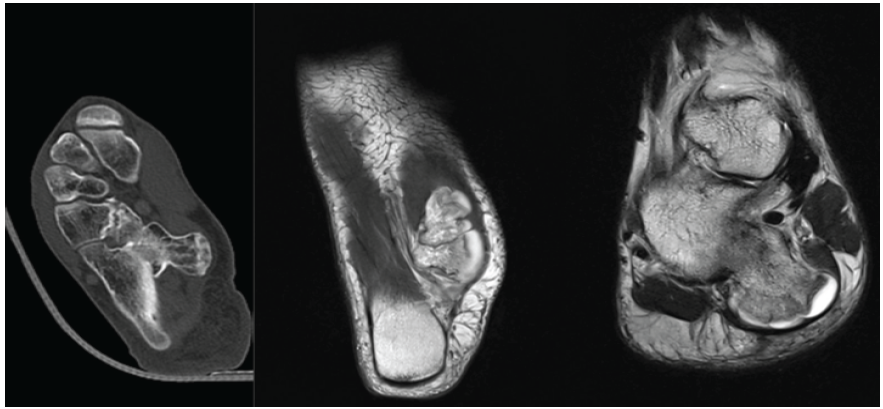

To further delineate the lesion and assess its exact morphology, a CT scan was obtained, which confirmed the pedunculated nature of the lesion, measuring 4.3 × 3.5 × 2.8 cm. MRI of the right ankle was also performed to evaluate the cartilage cap and surrounding soft tissues (Fig. 2).

Figure 2: Computed tomography/magnetic resonance imaging confirming cortex-medullary continuity and cartilage cap.

The lesion was seen to be covered by a cartilage cap measuring 4.9 mm in thickness. No evidence of malignant transformation or soft-tissue invasion was noted.